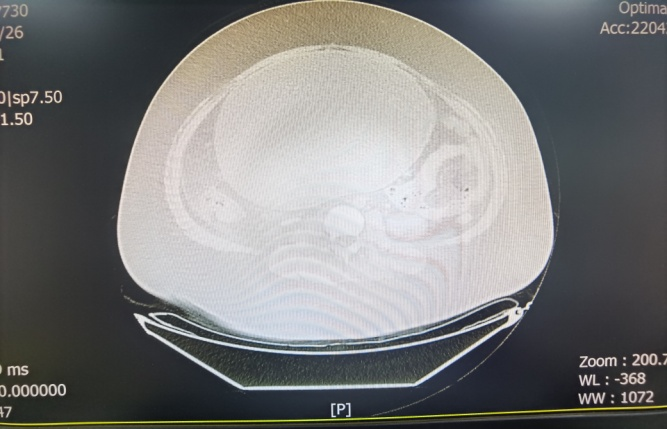

病例二:16岁女孩小平(化名),因“下腹痛2天”来我院就诊,小平身高168cm,体重高达125公斤,查体可扪及盆腹腔一巨大包块,上界高达剑突二指,宽达两侧腋中线,表面光滑、活动度可、轻压痛,血液肿瘤指标均不高。CT提示腹腔内28.4 cm×22.8cm×17.4 cm囊性占位,考虑为右侧附件来源。妇科医护团队经过紧急进行病情评估和细致的查房,考虑小平罹患卵巢囊肿蒂扭转可能性大,有明确急诊手术指征,在手术方式选择上,考虑患儿年龄小,体型肥胖,卵巢囊肿巨大,如果选择开腹手术,即使是经腹小切口手术,术后腹壁切口脂肪液化、切口愈合不良,甚至术口裂开,二期缝合等风险均较高,影像学下判断卵巢囊肿囊内容物以液性为主,考虑为良性肿瘤,故决定选择腹腔镜下手术。

术前增强CT检查